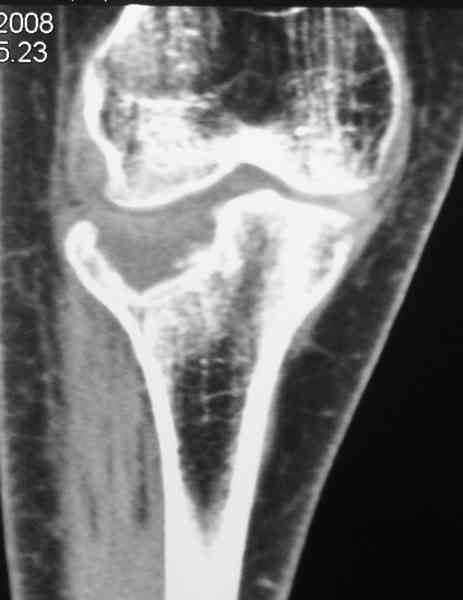

Есть ли возможность сделать КТ?

К большому сожалению КТ пока на ремонте, как запустять, сразу сделаю. Спасибо.

Я согласен с мнением доктора Соломина, что необходимо выполнить СТ. Это поможет Вам не только определить степень повреждения твёрдых тканей, но и увадеть степень сращения. Без СТ не возможно планировать дальнейшую тактику лечения.

У пациента основной проблемой является импрессионый перелом наружного мыщелка, уже неправильно сросшийся, по-видимому. Аппаратом закрыто можно только подправить угол на уровне метадиафиза. Что

улучшит разве что внешний вид конечности, но не решит основной проблемы - грубой деформации суставной поверхности.

Уважаемый Абдурашид. Если нет противопоказаний , то из оперативных способов, я бы рекомендовал следующие: Полное замещение наружного мыщелка аллотрансплантатом либо открытая репозиция с элевацией и замещение дефекта ауто или аллокостью. В Ваших условиях , я бы рекомендовал второй способ. Во-время элевации необходимо разъединить фрагменты со стороны сустава ( надсечь скальпелем по линиям перелома, а затем тонким остеотомом их разъединить. При помощи долота произвести неполную остеотомию ( захватите не менее 1,5 - 2 см губчатой кости и поднять фрагменты, визуально отрепонировать и фиксировать 2-3 спицами. Дефект заместить костным ауто или аллатрансплантатом. Окончательная стабилизация пластиной ( лучше с угловой стабильностью, либо АВФ - позволит спокойно устранить угловую деформацию.

Через 3 месяца после перелома все еще можно выделить отломки, очистить от костной мозоли и и восстановить анатомию суставной поверхности. Фиксировать компрессионными шурупами. Важно помнить, что наружный мыщелок должен быть на 4-5 мм выше внутреннего. Передняя крестообразная связка обычно остается с частью кости и важно фиксировать ее проволокой по Ли. После восстановления суставной поверхности весь комплекс суставной поверхности нужно фиксировать к диафизу, можно использовать пластинку с фиксированными шурупами с наружной поверхности или две обычные с двух сторон или аппарат Илизарова. Важно сохранить задний наклон плато приблизительно 7 градусов. При закрытии доступа бугристость б.б кости фиксировать двумя шурупами. Важно добиться стабильности для максимально ранней разработки. Операция сложная, но интересная.